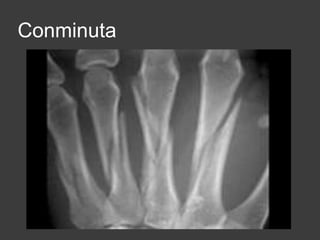

conminuta

Conminuta